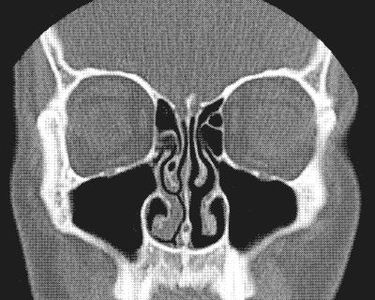

鼻の奥にある鼻甲介(びこうかい)と呼ばれるところが片方ずつ膨張することによって交互に呼吸しているのですが、これは自律神経によってコントロールされているとのことです。